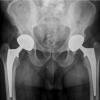

Case Image & Technology corner